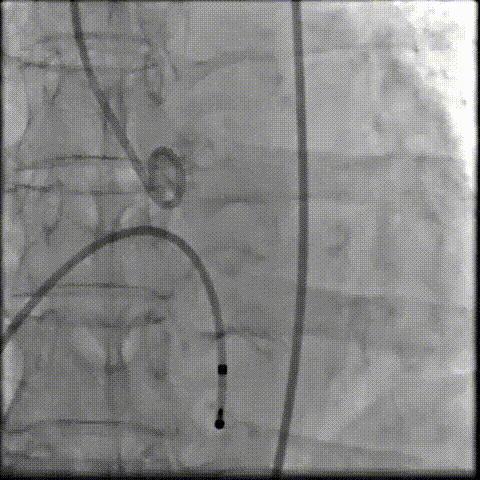

术中影像

根部造影可见返流;20mm球囊预扩,LCA灌注缝隙狭小

预置LCA保护;第一次释放,

团状钙化挤压导致瓣膜(AV23)少量下滑

回收后重新定位,第二次释放,

瓣膜(AV23)深度仍未达到最佳预期

完全回收,第三次定位释放,瓣膜(AV23)位置良好